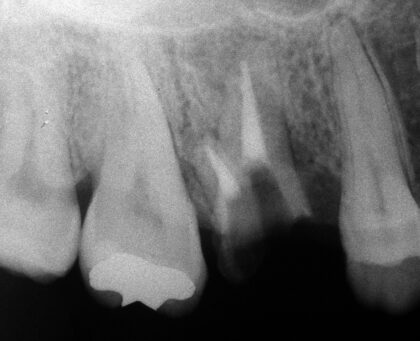

移植前

重度虫歯の右上6番の歯に、右上の親知らず(8番目)を移植しました。

移植後